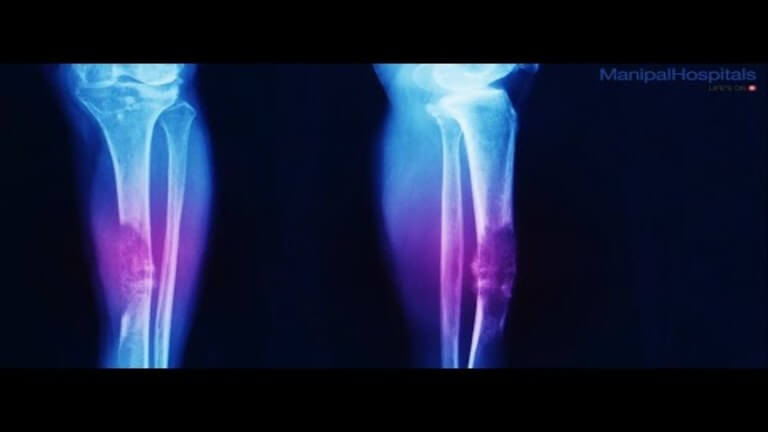

3. Oncology treatments such as chemotherapy, breast cancer surgery, prostate cancer surgery, intensity-modulated radiation therapy, etc.

There is no shortage of advanced medical facilities in Manipal Hospitals. Here doctors use state-of-the-art technology and innovative methods to perform complex surgeries for patients coming from Nigeria.